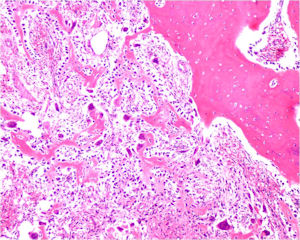

Gross Pathology

The gross pathology of an osteoblastoma is indistinguishable from an osteoid osteoma except larger

- Nidus is well demarcated

- Granular, friable, reddish hemorrhagic tissue

- May bleed significantly when curetted

- Cortex is thinned, possibly destroyed

Microscopic Pathology

- Interlacing network of bone trabeculae in a loose fibrovascular stroma

- Prominent vessels

- Soft tissue component usually surrounded by shell of reactive bone or periosteum (Egg Shell Rim of Calcification)